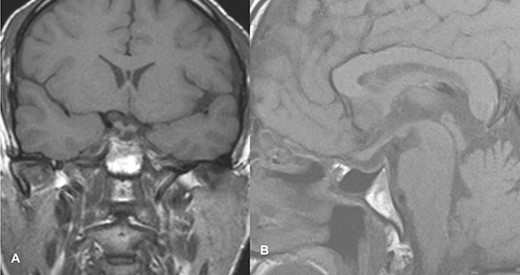

The patient underwent transsphenoidal pituitary adenectomy 3 days after admission. Intraoperatively, soft tumors with hemorrhagic components were seen. Hemostasis was achieved and the sella was packed with fat. The patient was managed in the ICU for 2 days and discharged on the 8th postoperative day. The ptosis gradually improved within 2 days of surgery, and during the 2-week follow-up in the outpatient clinic, the ptosis recovered completely. Follow-up imaging showed no evidence of a residual lesion in sella turcica (Fig. 4).

Follow-up imaging of case 2 showed no evidence of a residual lesion in sella turcica.